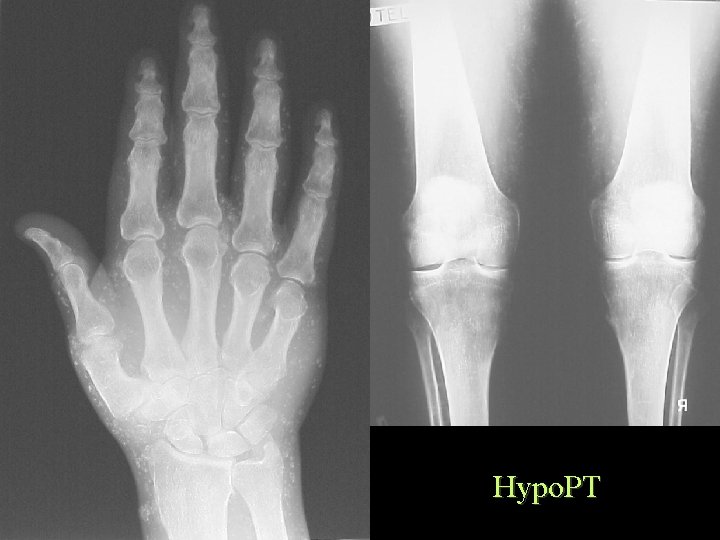

Soft Tissue Calcification By Cause Metastatic Calcification • Hyperparathyroidism • • • Hypoparathyroidism Renal Osteodystrophy Hypervitaminosis D Milk Alkali Sarcoidosis Massive bone destruction – Mets. , Myeloma, Leukaemia

Hypo. PT